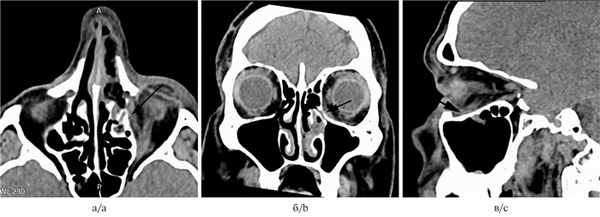

На следующий день после операции была проведена компьютерная томография средней зоны лица (рис. 1, б). На сканограммах определяли послеоперационный дефект костной стенки размером 11×9 мм. Сохранялся небольшой экзофтальм слева: задний полюс левого глазного яблока располагался на 7 мм кзади от уровня межскуловой линии, задний полюс правого глазного яблока — на 8,8 мм. Определяли умеренное уплотнение параорбитальной и ретробульбарной клетчатки в нижних отделах левой орбиты, уплотнение мягких тканей в области левого слезного мешка. Изменений со стороны глазодвигательных мышц выявлено не было. Зрительные нервы симметричные. Определена гематома в нижнемедиальном отделе орбиты (рис. 2). Слизистая оболочка левой верхнечелюстной пазухи, а также в передних левых клетках решетчатого лабиринта и в нижней части левой лобной пазухи умеренно утолщена. Полость носа тампонирована.

Рис. 2. Результаты компьютерной томографии, выполненной в 1-е сутки после операции (мягкотканная реконструкция).

а — аксиальная проекция; б — коронарная проекция; в — кососагиттальная проекция

Стрелкой обозначена гематома.

При компьютерной статической периметрии (скрининговая программа) и при исследовании цветовой чувствительности изменений не выявлено. При экзофтальмометрии по Hertel был обнаружен остаточный экзофтальм 1 мм.